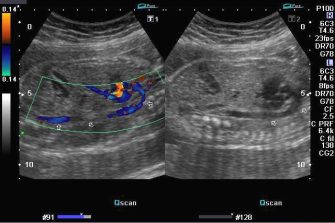

Doppler image of fetal aorta © Dr. Joe Antony

Maternal Fetal Medicine Research Group

The Maternal Fetal Medicine Research Group uses technology to detect at-risk fetus’ targeting in utero therapy or intervention.